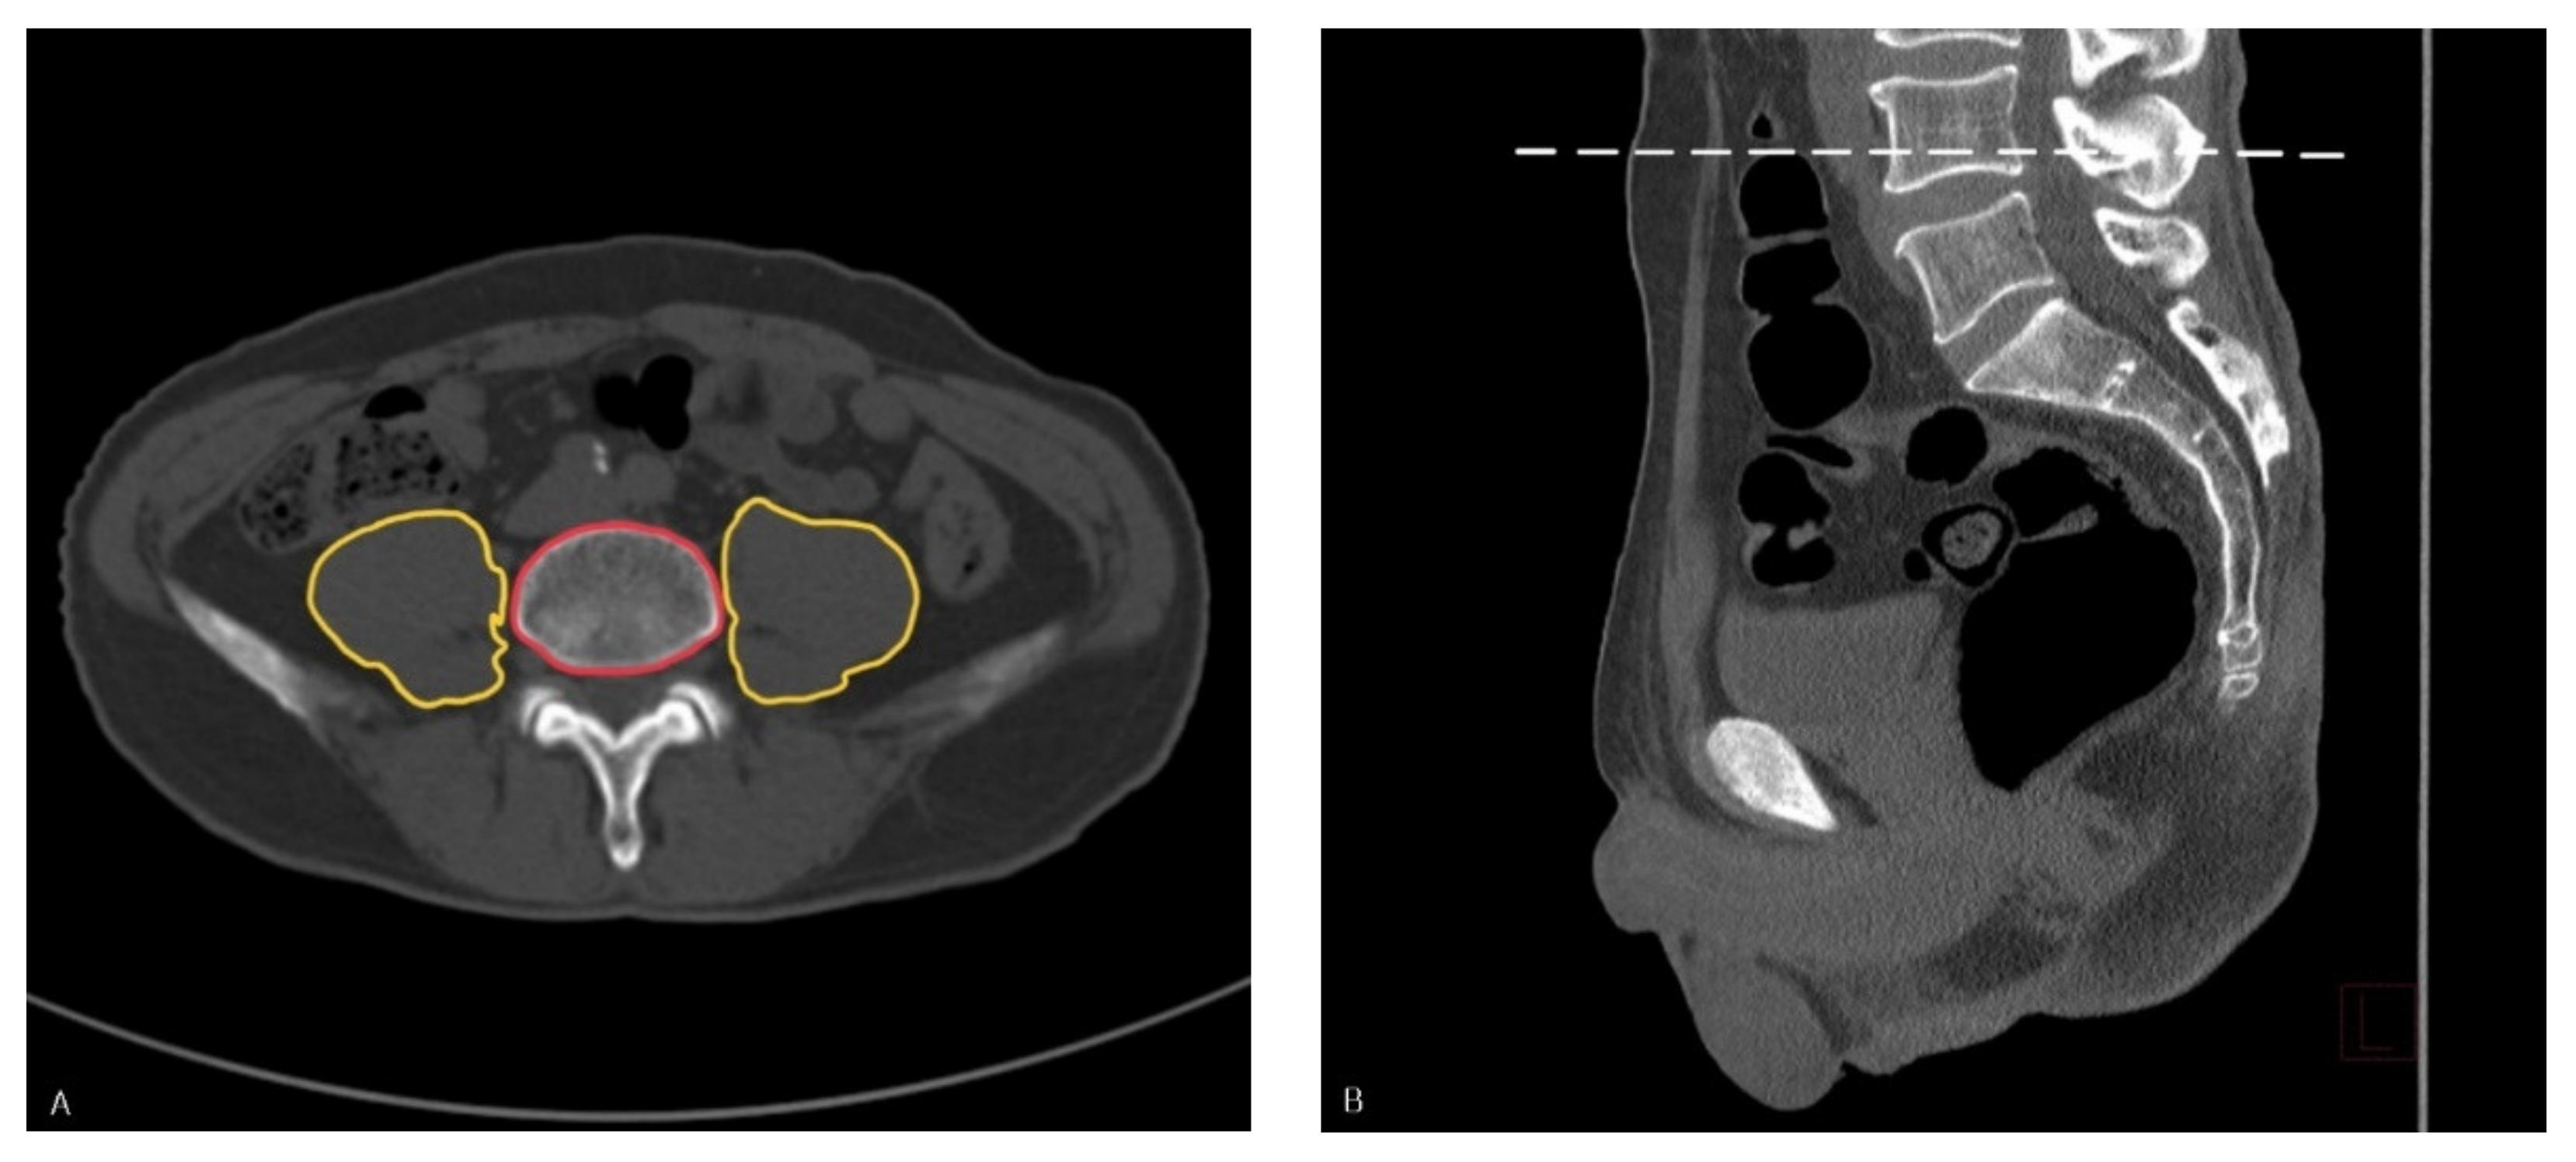

2.2. Measurements